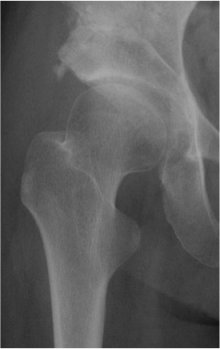

変形性股関節症は先天性股関節脱臼や生まれつき臼蓋(股関節の屋根の部分)のかぶりが悪く、長年股関節に負担がかかっていたため、関節表面の軟骨がすり減って股関節が変形し股関節の痛みや歩行障害の原因となる病気です。そのほか原因不明のものや大腿骨頭壊死、けがのあとにも変形性股関節症が生じる可能性があります。変形の程度により”前期,初期,進行期、末期”と4つの病気の状態に分けられます。この変形の程度にくわえて、股関節の状態、年齢、患者さんの社会的要因(仕事、家庭の事情)などを考慮して治療法が決定されます。

寛骨臼回転骨切り術(RAO)

末期の状態になれば股関節を人工物に入れ替えるしか治療法がなくなります。しかし、前期や初期の状態であれば条件さえあえば自分の骨を利用した手術により、変形をくいとめ十分に機能を回復させることが可能と考えます。 手術は臼蓋(骨盤)の骨をくり抜きこれを回転させることで股関節のかぶりを良くするものです。術後はリハビリテーションプログラムに従ってリハビリを行い、入院は1ヵ月半から2カ月必要です。また手術後の筋力などの回復には半年以上を要します。